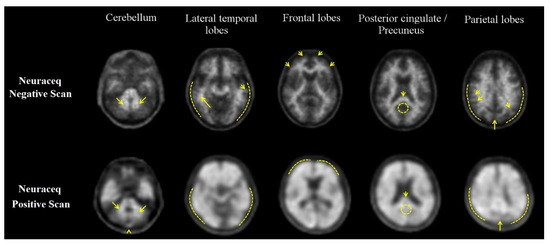

3.1. Visual Assessment